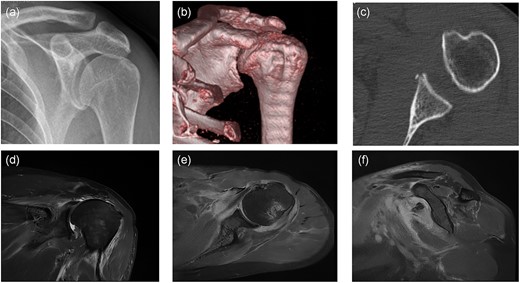

Left shoulder joint X-ray, three-dimensional CT (3D CT), and magnetic resonance imaging (MRI) were performed after admission. X-ray and 3D CT scanning revealed an upward shift of the left humeral head, fracture of the anterior inferior glenoid of the left shoulder, and Hill-Sachs injury of the posterolateral left humeral head (Fig. 2a–c). MRI scanning revealed the left humeral head moved up obviously and the subacromial space of the shoulder decreased. The distance between the acromion and humeral head was about 4 cm. The supraspinatus tendon retracted ~4 cm, and the anterior and posterior lacerations were ~4 cm in size. The involved tendons were supraspinatus, infraspinatus, and subscapular, but were not accompanied by significant muscle atrophy and fat infiltration (Fig. 2d–f).

Preoperative imaging: (a) anteroposterior X-ray of the left shoulder; (b) anteroposterior CT 3D reconstruction of the left shoulder; (c) coronal CT radiograph of the left shoulder; (d) anteroposterior MRI of the left shoulder; (e) coronal MRI of the left shoulder; (f) sagittal MRI of the left shoulder.